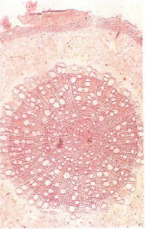

【标题】 两面针 【拼音】 Liangmianzhen 【英文】 RADIX ZANTHOXYLI 【概述】 本品为芸香科植物两面针Zanthoxylum nitidum (Roxb.) DC. 的干燥根。全年均可采挖,洗净,切片或段,晒干。 【性味归经】 苦、辛,平;有小毒。归肝、胃经。 【应用】 行气止痛,活血化瘀,祛风通络。用于气滞血瘀引起的跌打损伤、风湿痹痛、胃痛、牙痛,毒蛇咬伤;外治汤火烫伤。 【注意】 不能过量服用。忌与酸味食物同服。 【贮藏】 置干燥处,防潮,防蛀。 【用法用量】 5~10g。外用适量,研末调敷或煎水洗患处。 【理化鉴别】 (1) 本品横切面:木栓层为10~15列木栓细胞。韧皮部有少数草酸钙方晶及油细胞散在,油细胞长径52~122μm,短径28~87μm;韧皮部外缘有木化的纤维, 单个或 2~5 个成群。木质部导管直径35~98μm,周围有纤维束;木射线宽 1~3 列细 胞,有单纹孔。薄壁细胞充满淀粉粒。 (2) 取两面针对照药材1g,加乙醇15ml,温浸30分钟,超声处理30分钟,滤过,滤液蒸干,残渣加乙醇1ml 使溶解,作为对照药材溶液。照薄层色谱法(附录Ⅵ B)试验, 吸取对照药材溶液和[含量测定]项下的供试品溶液、对照品溶液各2μl,分别点于同一 硅胶G薄层板上,置以苯-醋酸乙酯-甲醇-异丙醇-浓氨试液(20 :5 :3 :1 :0.12) 为展 开剂的展开缸中饱和10分钟, 展开,取出,晾干,置紫外光灯(365nm) 下检视。供试 品色谱中,在与对照药材色谱相应的位置上,显相同颜色的荧光斑点;在与对照品色谱 相应的位置上,显相同的浅黄色的荧光斑点。 (3) 取乙氧基白屈菜红碱对照品,加甲醇配制成每1ml含1mg的溶液,作为对照品溶液。照薄层色谱法(附录Ⅵ B)试验,吸取对照品溶液、[鉴别](2) 项下的对照药材溶 液和[含量测定]项下的供试品溶液各 2μl ,分别点于同一硅胶G薄层板上,以甲苯- 醋酸乙酯-甲醇(25 :2 :0.1)为展开剂,置以浓氨试液预饱和10分钟的展开缸内,展开, 取出,晾干,置紫外光灯(365nm) 下检视。供试品色谱中,在与对照药材色谱相应的位 置上,显相同颜色的荧光斑点;在与对照品色谱相应的位置上,显相同的橘黄色荧光斑点。 【含量测定】 取本品粗粉约1g〔同时另取本品粉末测定水分(附录Ⅸ H第一法〕,精密称定,置索氏提取器中,加甲醇100ml,加热回流提取至回流液无色。提取液回收甲醇 至约2ml,转移至10ml量瓶中,加甲醇至刻度,摇匀,作为供试品溶液。另取氯化两面针碱 对照品适量,精密称定,加甲醇制成每1ml 含0.5mg 的溶液,作为对照品溶液。照薄层色 谱法(附录Ⅵ B)试验,精密吸取供试品溶液4μl、对照品溶液1μl与4μl,分别交叉点 于同一以羧甲基纤维素钠为黏合剂的硅胶G薄层板上,以苯-醋酸乙酯-甲醇-异丙醇- 浓氨试液(20 :5 :3 :1 :0.12) 为展开剂,展开,取出,晾干,置紫外光灯(365nm) 下检视。 照薄层色谱法(附录Ⅵ B薄层扫描法)进行扫描,波长:λS=300nm,λR=210nm,测量供试 品吸收度积分值与对照品吸收度积分值,计算,即得。 本品按干燥品计算,以两面针碱(C21H18NO4)计,不得少于0.25%。 【性状】 本品为厚片或圆柱形短段,长2~20cm,厚0.5~6(10)cm。表面淡棕黄色或淡黄色,有鲜黄色或黄褐色类圆形皮孔。切断面较光滑,皮部淡棕色,木部淡黄色, 可见同心性环纹及密集的小孔。质坚硬。气微香,味辛辣麻舌而苦。 【图片】 两面针 ![]() 药材两面针 ![]() 药材两面针根横切面 ![]() (责任编辑:Doctor001) |